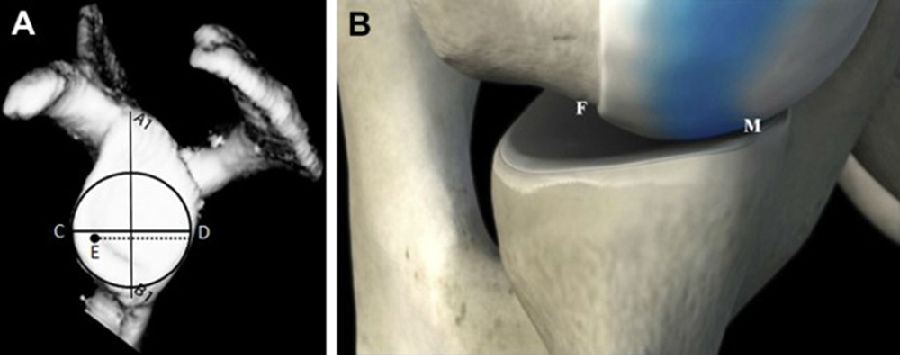

2014年Giovanni Di Giacomo提出轨迹内/轨迹外损伤,并以此提出分类及治疗策略。

图14

上图显示接触区域的内侧缘到肩袖止点的内侧缘的距离约为83%肩胛盂的宽度。A1-B1是肩胛盂的长轴,C-D是肩胛盂的宽度,E-D是肩胛盂轨迹,为83%肩胛盂的宽度。B图为盂肱关节在外展外旋位的对合关系,肱骨头和肩胛盂接触区域内侧边缘(M)到肩袖足印区的内侧边缘(F)的距离,是肩胛盂宽度的83%±14%。(肩胛盂轨迹=F-M=83%肩胛盂的宽度)。

图16

盂肱关节处于外展外旋位时,由于肱骨头的Hill-Sachs损伤和肩胛盂的骨缺失(双极骨缺失),Hill-Sachs损伤延伸到了肩胛盂轨迹内侧缘的内侧,肱骨头失去了肩胛盂前缘的骨性支持,此时我们称为轨迹外Hill-Sachs损伤。 盂肱关节处于外展外旋位时,如果Hill-Sachs损伤在肱骨头上的肩胛盂轨迹的内侧缘之内,我们称为轨迹内Hill-Sachs损伤。